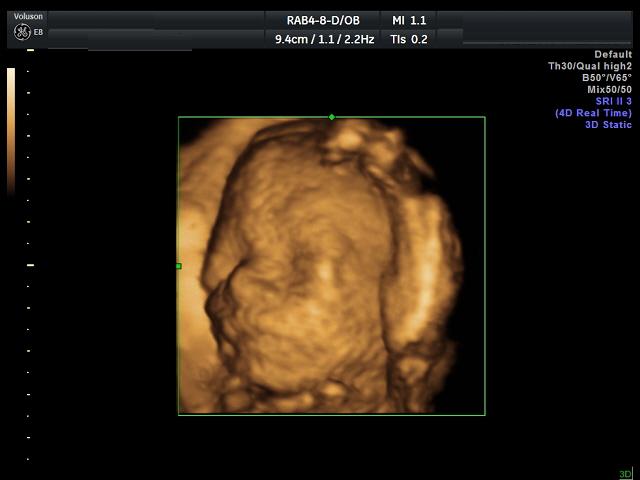

Ahojky byli jsme v nemocnici.........